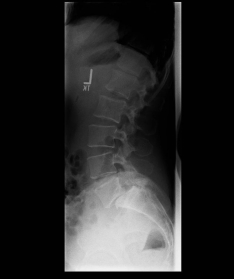

Spondylolisthese

X-ray image of a slipped vertebra in the lower lumbar spine before and after surgery